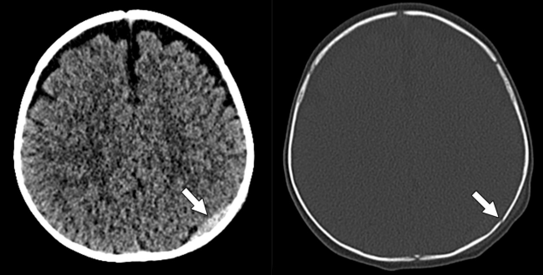

In the same way that NASA’s Apollo program sparked the development of new technologies (many of which were largely realized and appreciated years later) that landed the first humans on the moon, we are witnessing a fundamental transformation in health care operations that will be captured in future history books. Few could have predicted, for example, that CT scans would become an indispensable screening, diagnostic, staging, and management tool during a global pandemic. Providers have harnessed such a wide swath of tools—from laptops, mobile and wearable devices, and video conferencing to artificial intelligence, thermal sensors, and robots—to better serve patients and their loved ones, sustain remote reading and teaching environments, and uphold compliance and safety protocol. We now achieve efficiencies through rapid scanning, recruit new faculty through social media, teach our trainees in cloud-based classrooms, and attend national conferences with just a click—all without ever boarding a plane or even crossing clinical campuses.